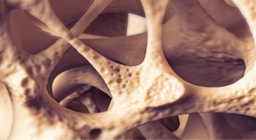

The bones of the skeletal system have various essential functions in the human body.